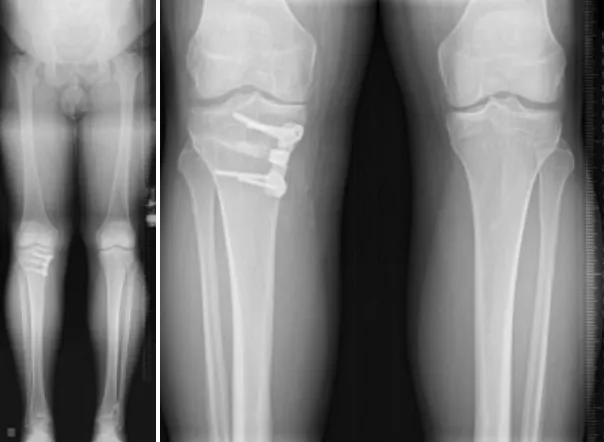

Is high tibial osteotomy major surgery?

Yes, high tibial osteotomy (HTO) is considered a major orthopedic surgery because it involves cutting and realigning the tibia. However, it is less invasive than total knee replacement and aims to preserve your natural joint. With modern techniques and experienced surgeons like Dr. Divya Ahuja, the risks are minimized, and recovery outcomes are excellent.

What is the ideal age for HTO surgery?

The ideal age is typically 40–60 years, when patients have early arthritis and good bone health. Younger patients with bow legs or deformities can also benefit. The key factor is the condition of the knee rather than age alone.

How successful is HTO surgery?

HTO has a success rate of over 85–90% in relieving pain and improving function. Results typically last 8–15 years, after which some patients may require a knee replacement.